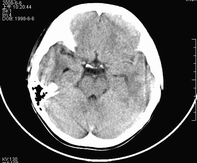

男,10岁,因近来常头痛就诊。先平扫拟诊右侧脉络膜裂囊肿,后薄层(3mm)扫描见此灶与右侧脑室后角相通,且向内几乎与鞍上池相连,并见一血管影沿其走形 (可能是脉络膜前动脉)。1。请教:脉络膜裂或脉络膜裂囊肿与侧脑室颞角或鞍上池相通吗?好像谁说脉络膜裂是脉络膜从外侧裂向侧脑室移行的裂隙。请高手讲讲这点的解剖关系。2。建议:对于老年患者,有丘脑附近特别是右丘脑附近的近似腔隙性梗死灶,临床症状不明显的,应做3mm薄层扫描,看病灶向下是否与侧脑室颞角相连,以免误诊。

薄层强化: